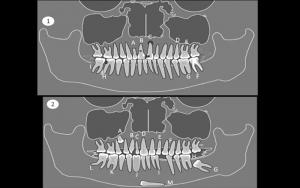

Todos os tópicos ministrados têm alicerce em bases científicas, sendo demostrados com casos clínicos fartamente ilustrados por fotografias de acompanhamento de todas as etapas do tratamento, comprovando a estabilidade dos resultados alcançados. Os diagnóstico serão realizados por meio de análise facial e cefalométrica e, quando necessário, usando modelos diagnósticos (set-up manual e virtual).